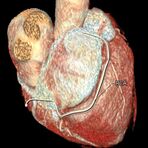

Herz

Durchführung am Standort im Diakonissenkrankenhaus